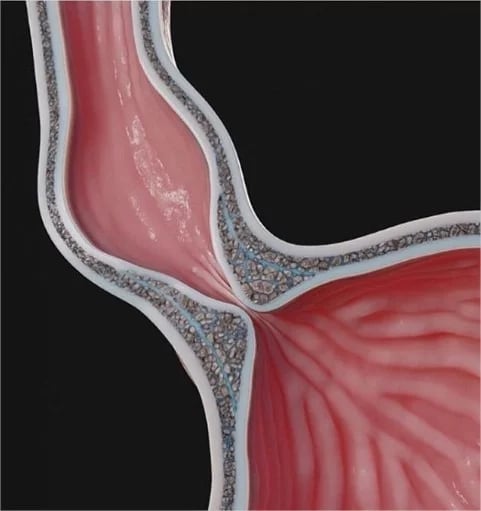

A acalasia é um distúrbio do esôfago que dificulta a passagem dos alimentos para o estômago, levando a engasgo, sensação de comida “parando” e perda de peso. No Brasil, além das causas sem origem definida, a Doença de Chagas é uma causa importante. O tipo de tratamento a ser realizado pode variar de acordo com a gravidade do problema, mas a cirurgia minimamente invasiva tem um papel muito importante para o tratamento desses pacientes.

A Doença do Refluxo Gastroesofágico causa sintomas como azia, queimação e regurgitação e nem sempre precisa ser controlada apenas com medicamentos por toda a vida. Em casos selecionados, a cirurgia de fundoplicatura (técnica que reforça a “válvula” entre esôfago e estômago) pode proporcionar alívio duradouro dos sintomas e reduzir a dependência de remédios. A decisão é tomada após uma avaliação cuidadosa, que pode incluir endoscopia e exames específicos. Agende uma consulta para entender se essa abordagem é adequada ao seu caso.